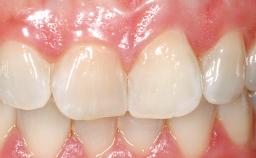

Early Placement of an Implant in a Maxillary Right Central Incisor Site

This 41-year-old female patient was referred to the clinic for the replacement of the right central incisor, since the tooth had developed a root fracture in the long axis that made extraction necessary. The healthy, non-smoking patient was first seen with the tooth still in place. A detailed Esthetic Risk Assessment was performed.The patient was worried about her dental esthetics and had high expectations for a successful treatment outcome from an esthetic point of view. The patient had a medium lip line that displayed parts of the gingiva in the anterior maxilla upon smile.

Abutment Type Customized

Prosthesis Type FDP

Defining Characteristics One missing tooth to be replaced by an implant-borne crown

Loading Protocol Conventional or early